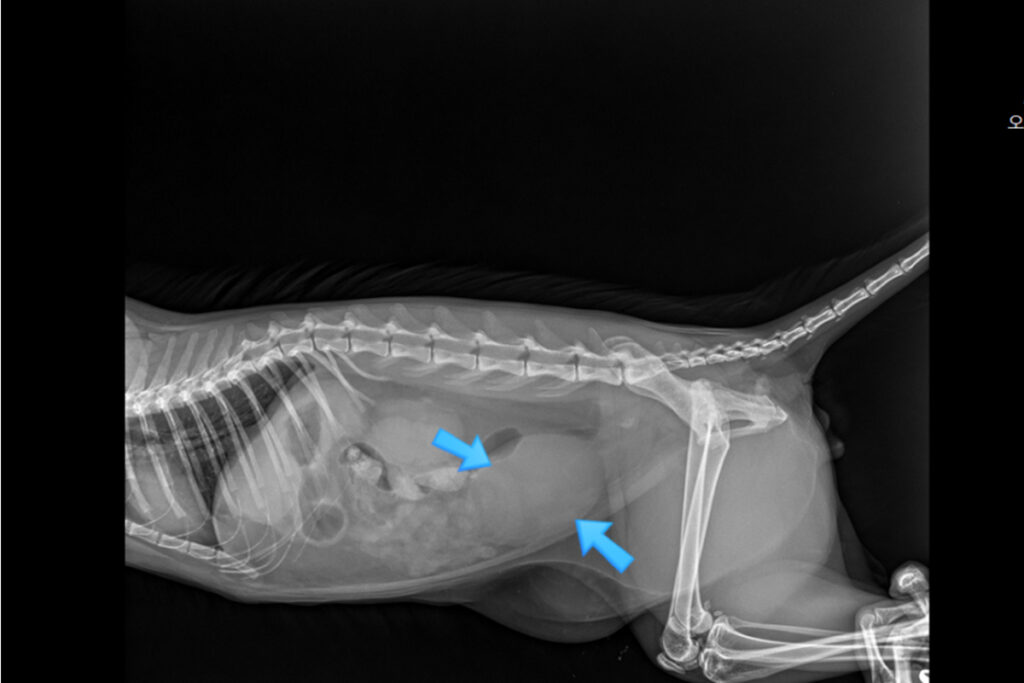

순환기 내과

심장은 전신 건강의 중심입니다.

심장 질환의 진행 단계와 아이의 상태를 고려해 약물 조절과 장기적인 심장 관리 치료를 시행합니다.